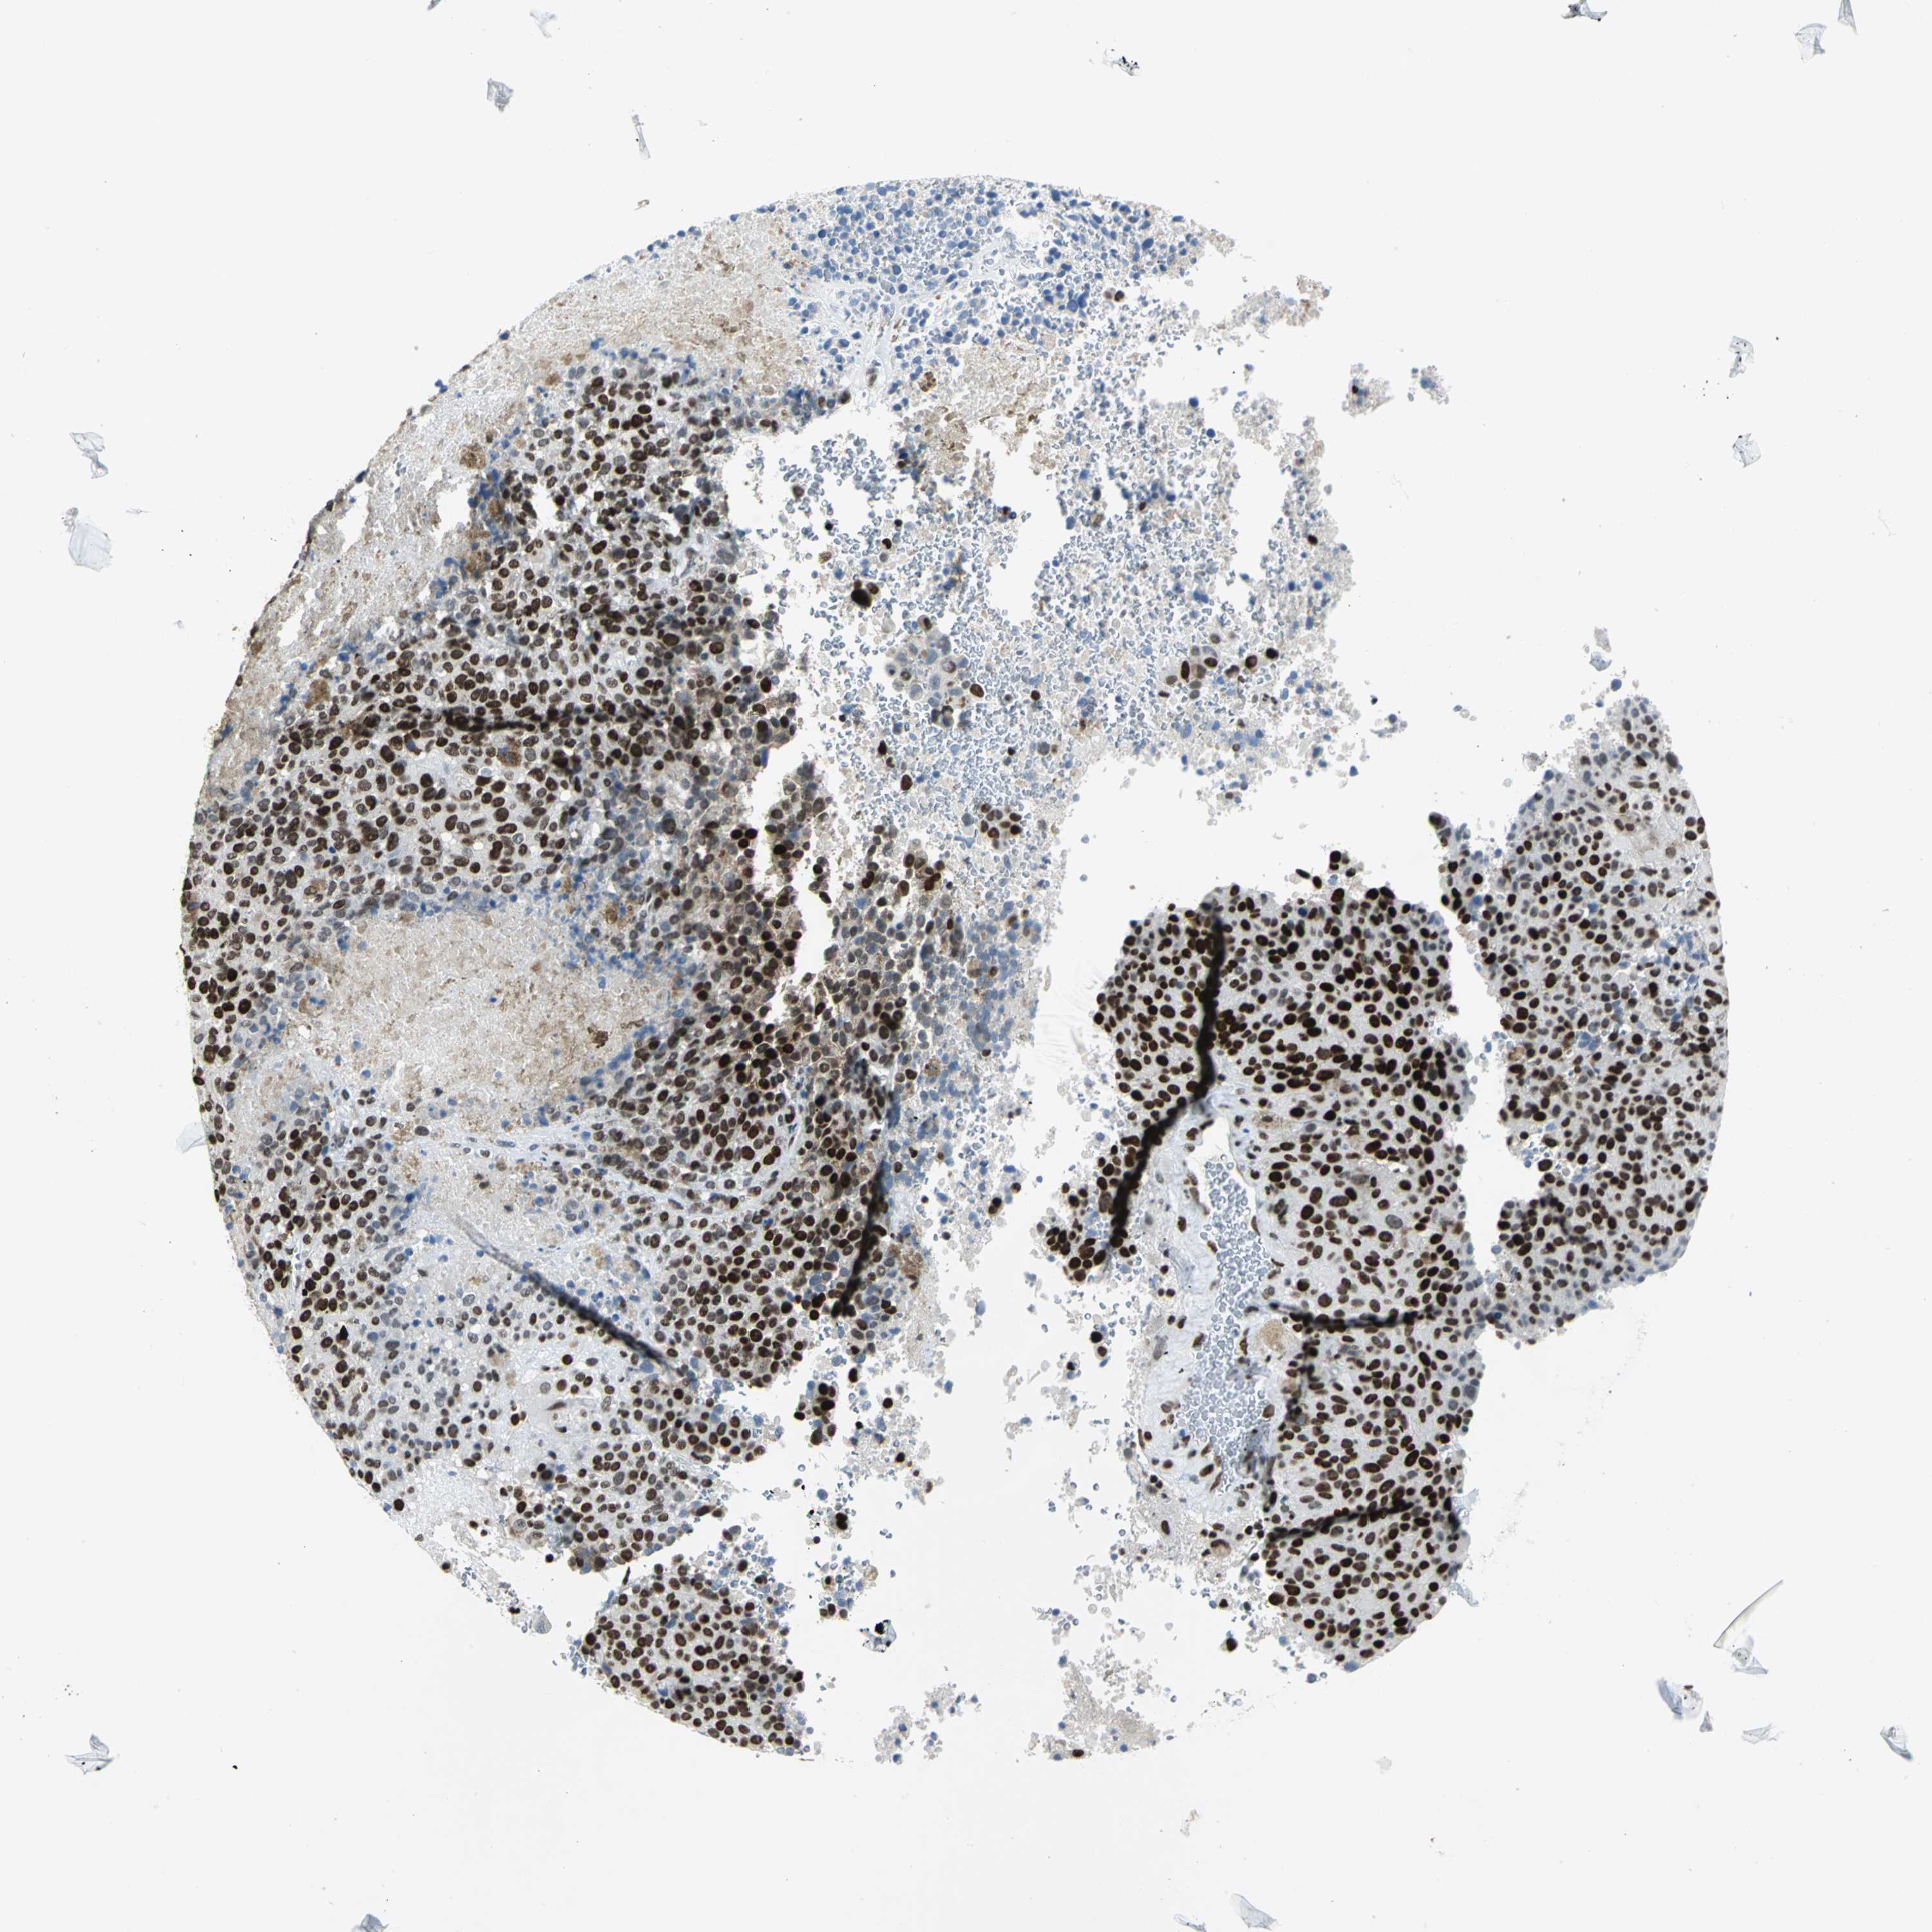

MELANOMA - Protein expressioni

A mouse-over function shows sample information and annotation data. Click on an image to view it in a full screen mode. Samples can be filtered based on level of antibody staining by selecting one or several of the following categories: high, medium, low and not detected. The assay and annotation is described here.

Note that samples used for immunohistochemistry by the Human Protein Atlas do not correspond to samples in the TCGA dataset.

Antibody stainingi

Antibody staining in the annotated cell types in the current human tissue is reported as not detected, low, medium, or high, based on conventional immunohistochemistry profiling in selected tissues. This score is based on the combination of the staining intensity and fraction of stained cells.

Each image is clickable and will lead to virtual microscopy that enables deeper exploration of all samples and also displays staining intensity scores, fraction scores and subcellular localization as well as patient and tissue information for each sample.

Antibody HPA004911

Staining

High

Medium

Low

Not detected

Intensity

Strong

Moderate

Weak

Negative

Quantity

>75%

75%-25%

<25%

None

Location

Nuclear

Cytoplasmic/membranous

Cytoplasmic/membranous,nuclear

Malignant melanoma, NOS

Malignant melanoma, Metastatic site